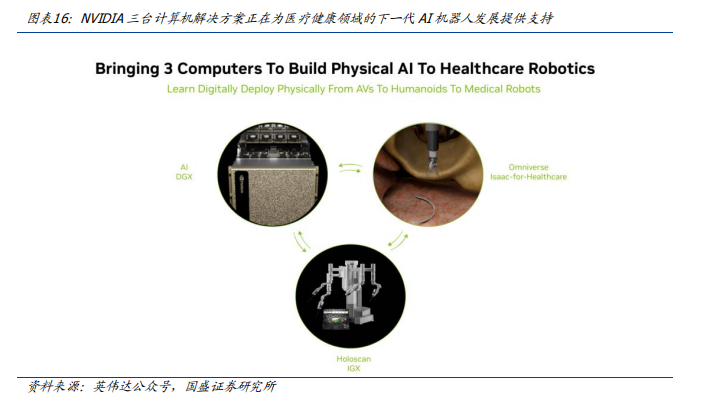

1)NVIDIA推出AI驱动的医疗机器人开发平台NVIDIAIsaacforHealthcare。

NVIDIAIsaacforHealthcare是一款用于AI医疗健康机器人的开发者框架,能帮助开发者应对这些挑战。IsaacforHealthcare适用于医疗健康特定领域,基于NVIDIA三台计算机实现物理AI。该框架包含用于采用MONAI提供预训练模型和代理式AI框架,其中MAISI、Vista-3D等模型可生成仿真工作流所需的解剖合成数据;其次,它包含用于仿真的NVIDIAOmniverse(包括NVIDIAIsaacSim和NVIDIAIsaacLab),开发者可以导入医疗设备/机器人、传感器及解剖结构,以构建具有物理精确性的虚拟环境,让机器人系统能安全地学习技能;第三,它包含NVIDIAHoloscan,用于实现在机器人端部署和进行实时传感器处理。该框架能够提供数字原型设计、硬件在环(HIL)产品开发测试、用于AI训练的合成数据生成、策略训练,以及实时部署等,适用于各类型医疗机器人,包括:

·手术与介入机器人

·影像诊断机器人

·康复辅助与服务机器人